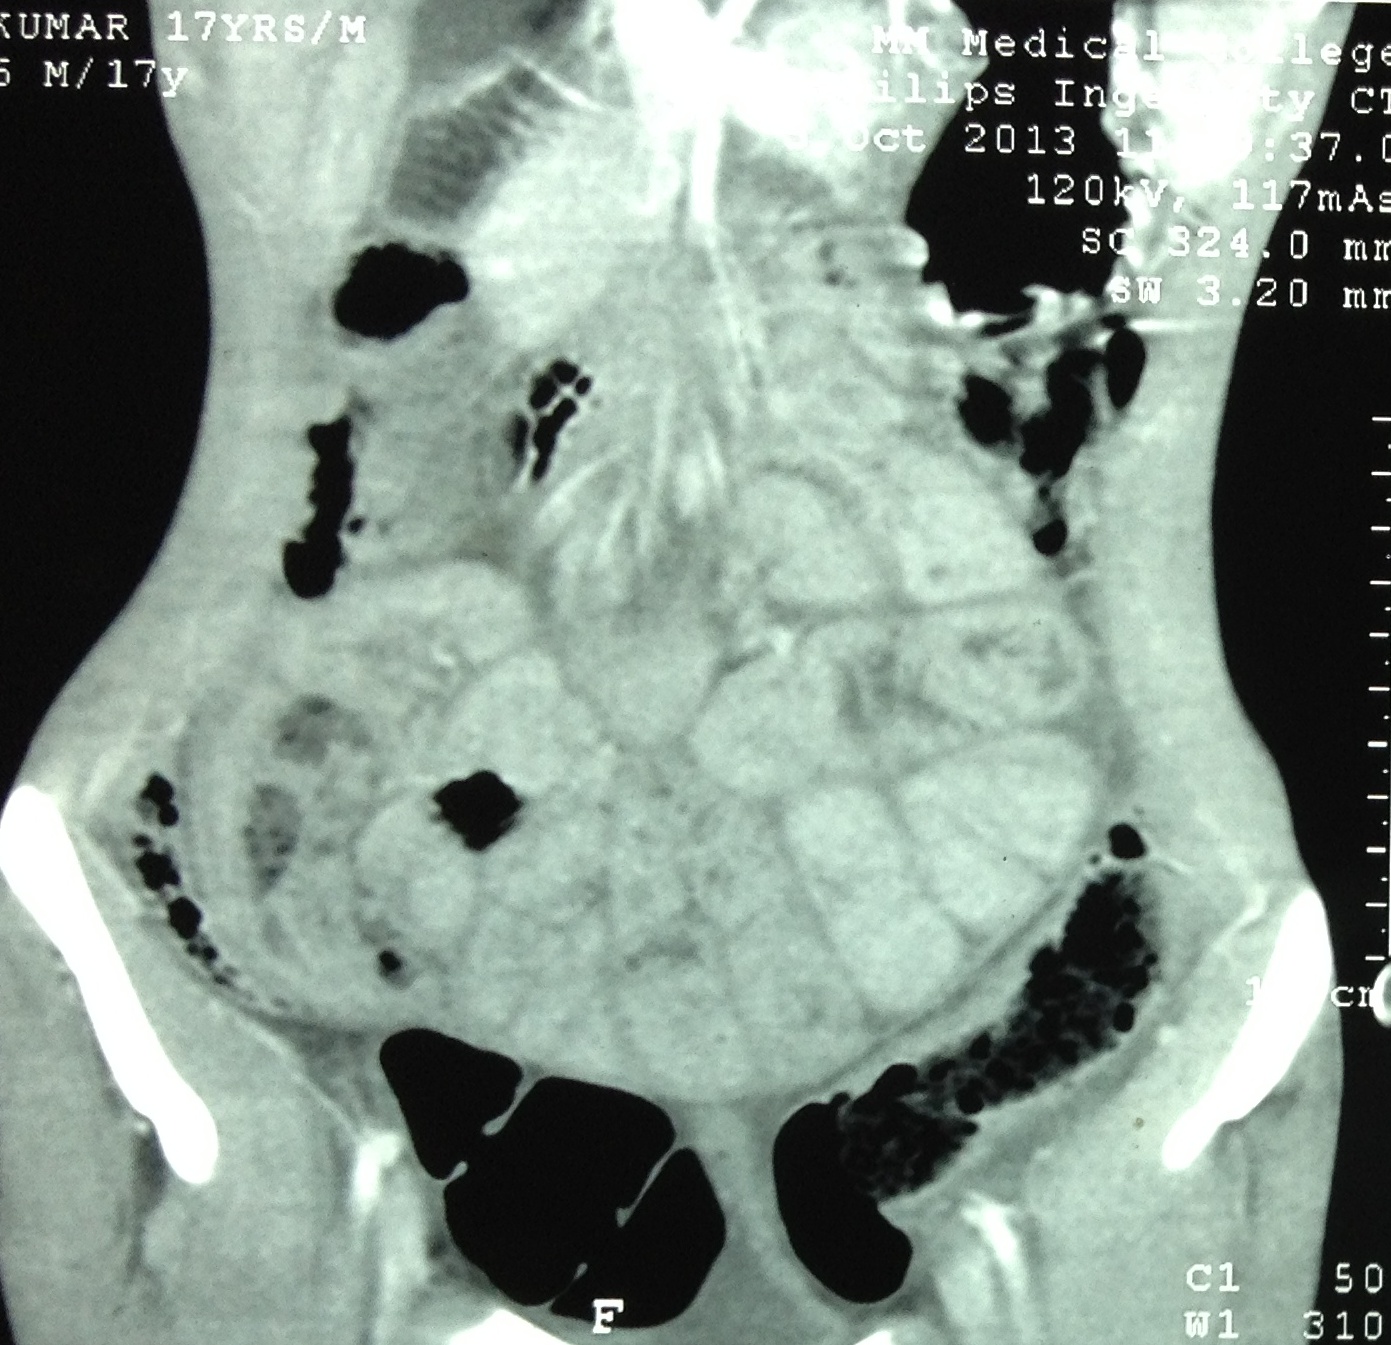

Material and methods. This study was carried out at M.M. Institute of Medical Sciences and Research, Mullana, Ambala, India between April 2013 – March 2016 in the Department of Pediatric Surgery. This is a prospective study. A total of 17 patients diagnosed with abdominal cocoon secondary to tuberculosis have been included in the study.

Results. A total of 17 patients presented to the emergency ward with features of acute intestinal obstruction. The average age was 15.3 years (range 9 years to 16 years). There were 14 females and 3 males. All patients presented with abdominal pain, bilious vomiting, constipation and abdominal distention. The patients were operated in our hospital and relieved of their obstruction. Based on their operative findings and after histopathological confirmation, patients were given ATT. In the follow-up, all patients did well, without recurrence of tuberculosis or intestinal obstruction.

Conclusion. Tuberculosis as a cause of childhood AC is rather common in developing countries and is potentially a fatal condition. A strong clinical suspicion, sonographic and computed tomography scan findings help establish a pre-operative diagnosis. Tuberculous AC has a strong prevalence in females. Surgery is the mainstay of treatment followed by anti-tuberculous drugs.